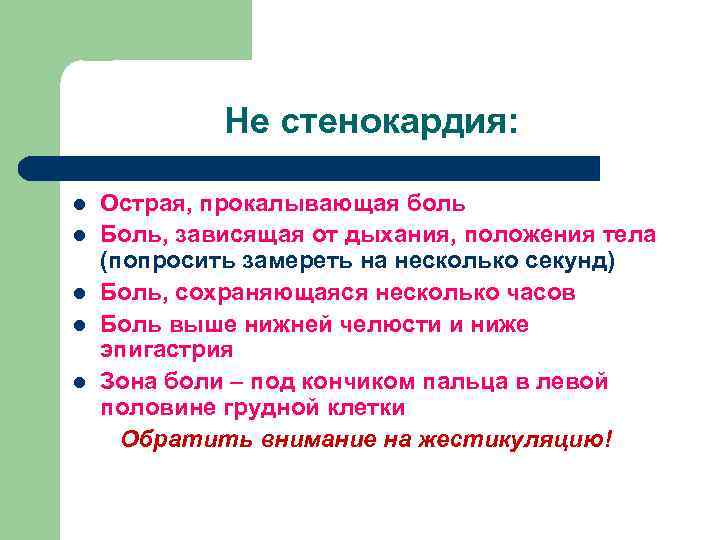

Не стенокардия: l l l Острая, прокалывающая боль Боль, зависящая от дыхания, положения тела (попросить замереть на несколько секунд) Боль, сохраняющаяся несколько часов Боль выше нижней челюсти и ниже эпигастрия Зона боли – под кончиком пальца в левой половине грудной клетки Обратить внимание на жестикуляцию!